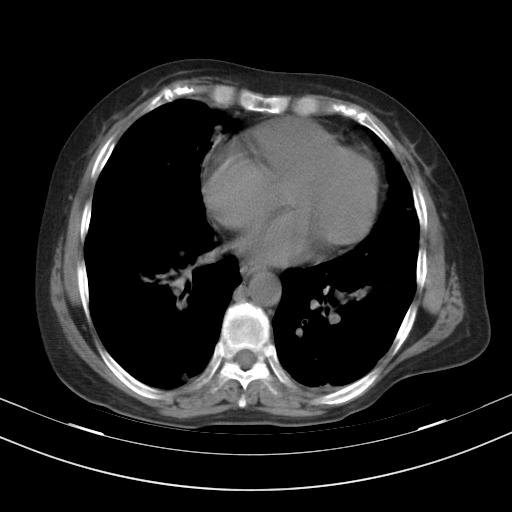

老年女性,嗜睡3天,意识模糊。轻咳,无发热。

两肺慢支炎伴感染,左侧胸腔积液。纵膈及双侧肺门淋巴结肿大建议复查。

1)两肺感染性病变;建议抗炎治疗后复查。2)纵隔淋巴结肿大。3)左侧胸腔积液。